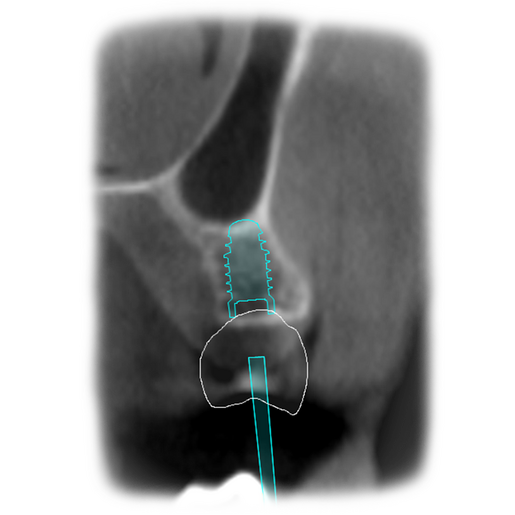

It is our most comprehensive planning option, and includes all the 3D treatment simulations needed for each case, such as ortho, perio, implants, grafts and orthognathic surgery.

Our 3D simulations showcase various treatment suggestions, facilitating a deeper understanding of the required procedures. This leads to the creation of a broader treatment plan and enables a more efficient communication with your patients.